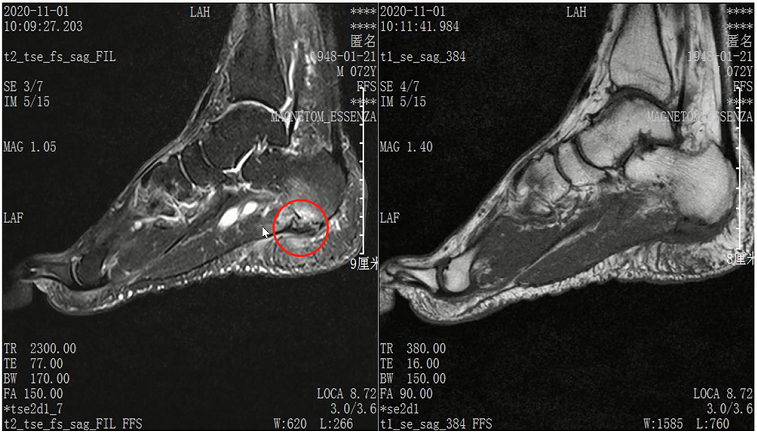

Lisfranc损伤在多发伤病人中常常容易漏诊,大约为 20-30%的漏诊率!